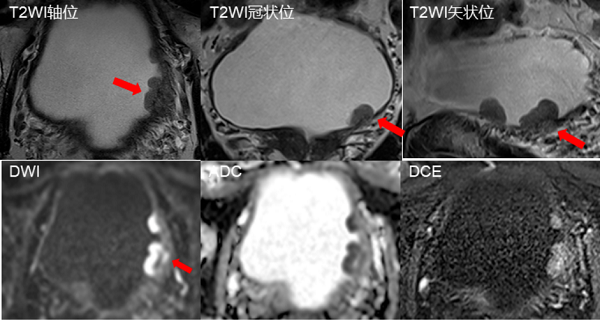

以mpMRI为基础开发的膀胱影像报告和数据系统(Ⅵ-RADS),通过综合评估肿瘤组织在T2加权、弥散加权(DWI)及动态增强等多个序列中的表现,对每个序列分别评分,最终得出综合的Ⅵ-RADS分值。

图片1

符合Ⅵ-RADS4分